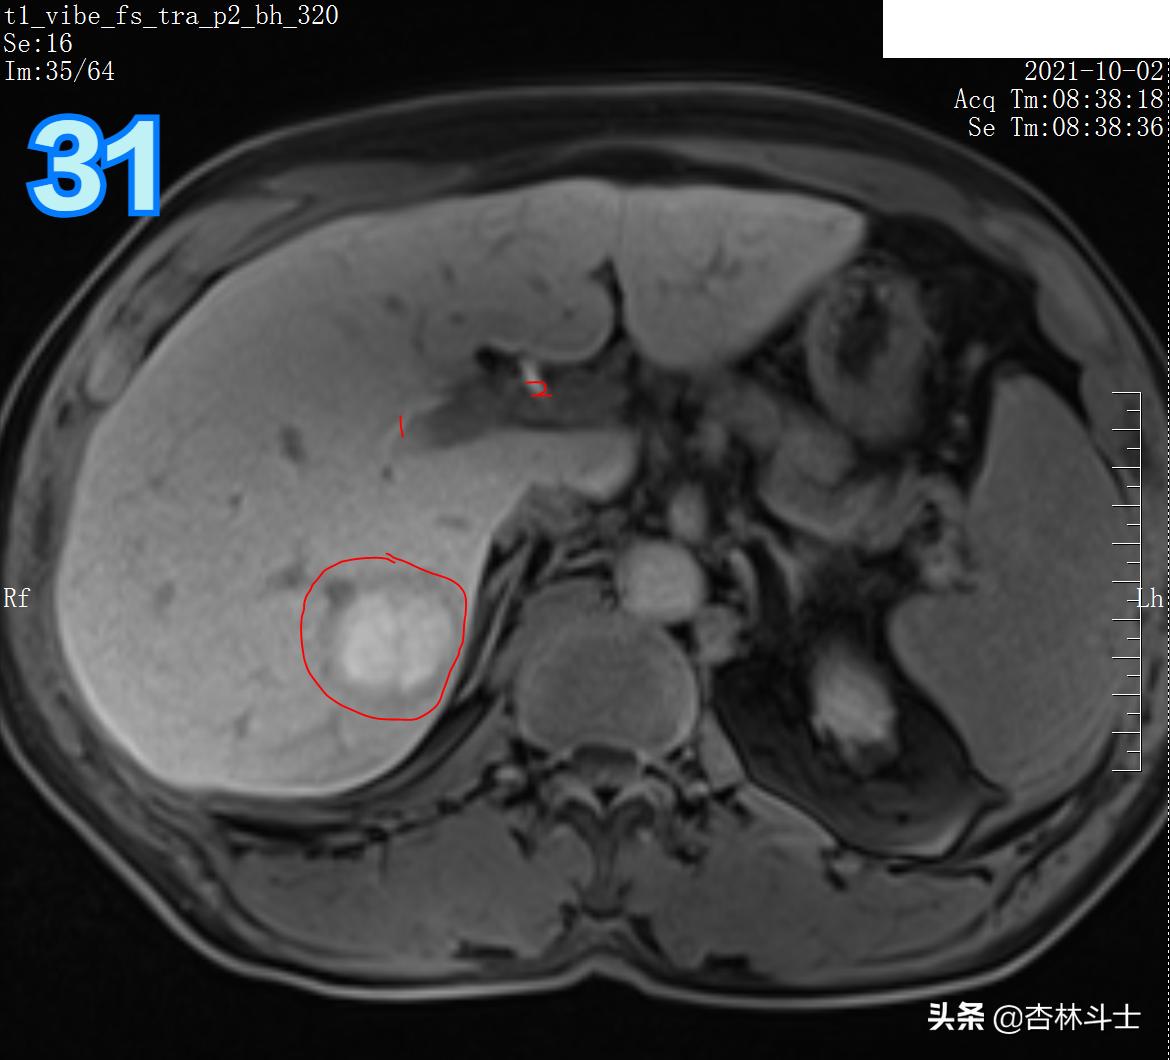

T1压脂肝胆特异期

图31 1、右肝管 2、左肝管

图32 1右肝管 2、门静脉右支 3、肝总管 4、门静脉主干

总结:10月份复查,肝右后叶下段新发一个直径约1㎝的结节,T1呈等信号,T2呈稍高信号,弥散加权序列可见弥散明显受限,增强动脉期明显均匀强化,门静脉期出现对比剂廓清,呈略低信号,平衡期信号进一步减低,肝胆特异期未见特异性对比剂摄取呈低信号。增强特征为典型的“快进快出”,影像学上典型的肝细胞癌表现。